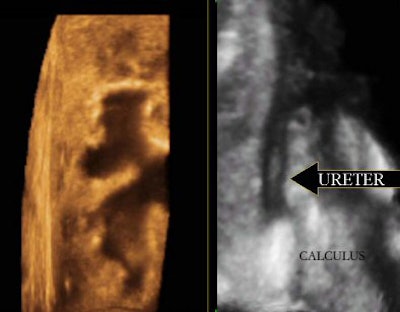

Fluid has always been the sonologist's friend, and 3D ultrasound has worked effectively in all fluid-filled structures. The virtual sonographic endoscopic views of the dilated calyceal systems and the urinary bladder have yielded spatial information about intraluminal lesions, their size, and their margins like never before. The presentation of information to the referring physician has also dramatically improved.

| Exquisite 3D reformation showing the dilated calcyceal system on the left and the dilated upper ureter with a calculus on the right. |